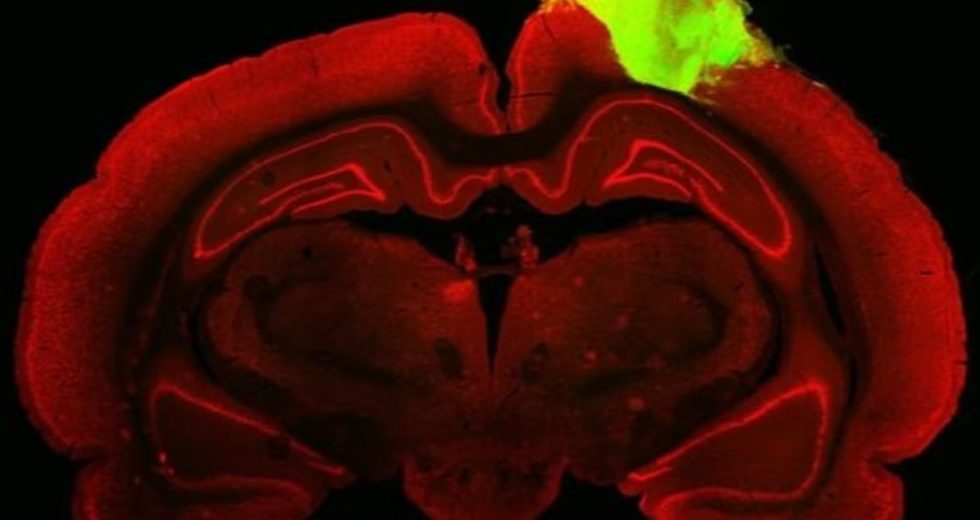

To try and treat blindness, scientists have successfully transferred a portion of a human brain into a rat’s brain. The…